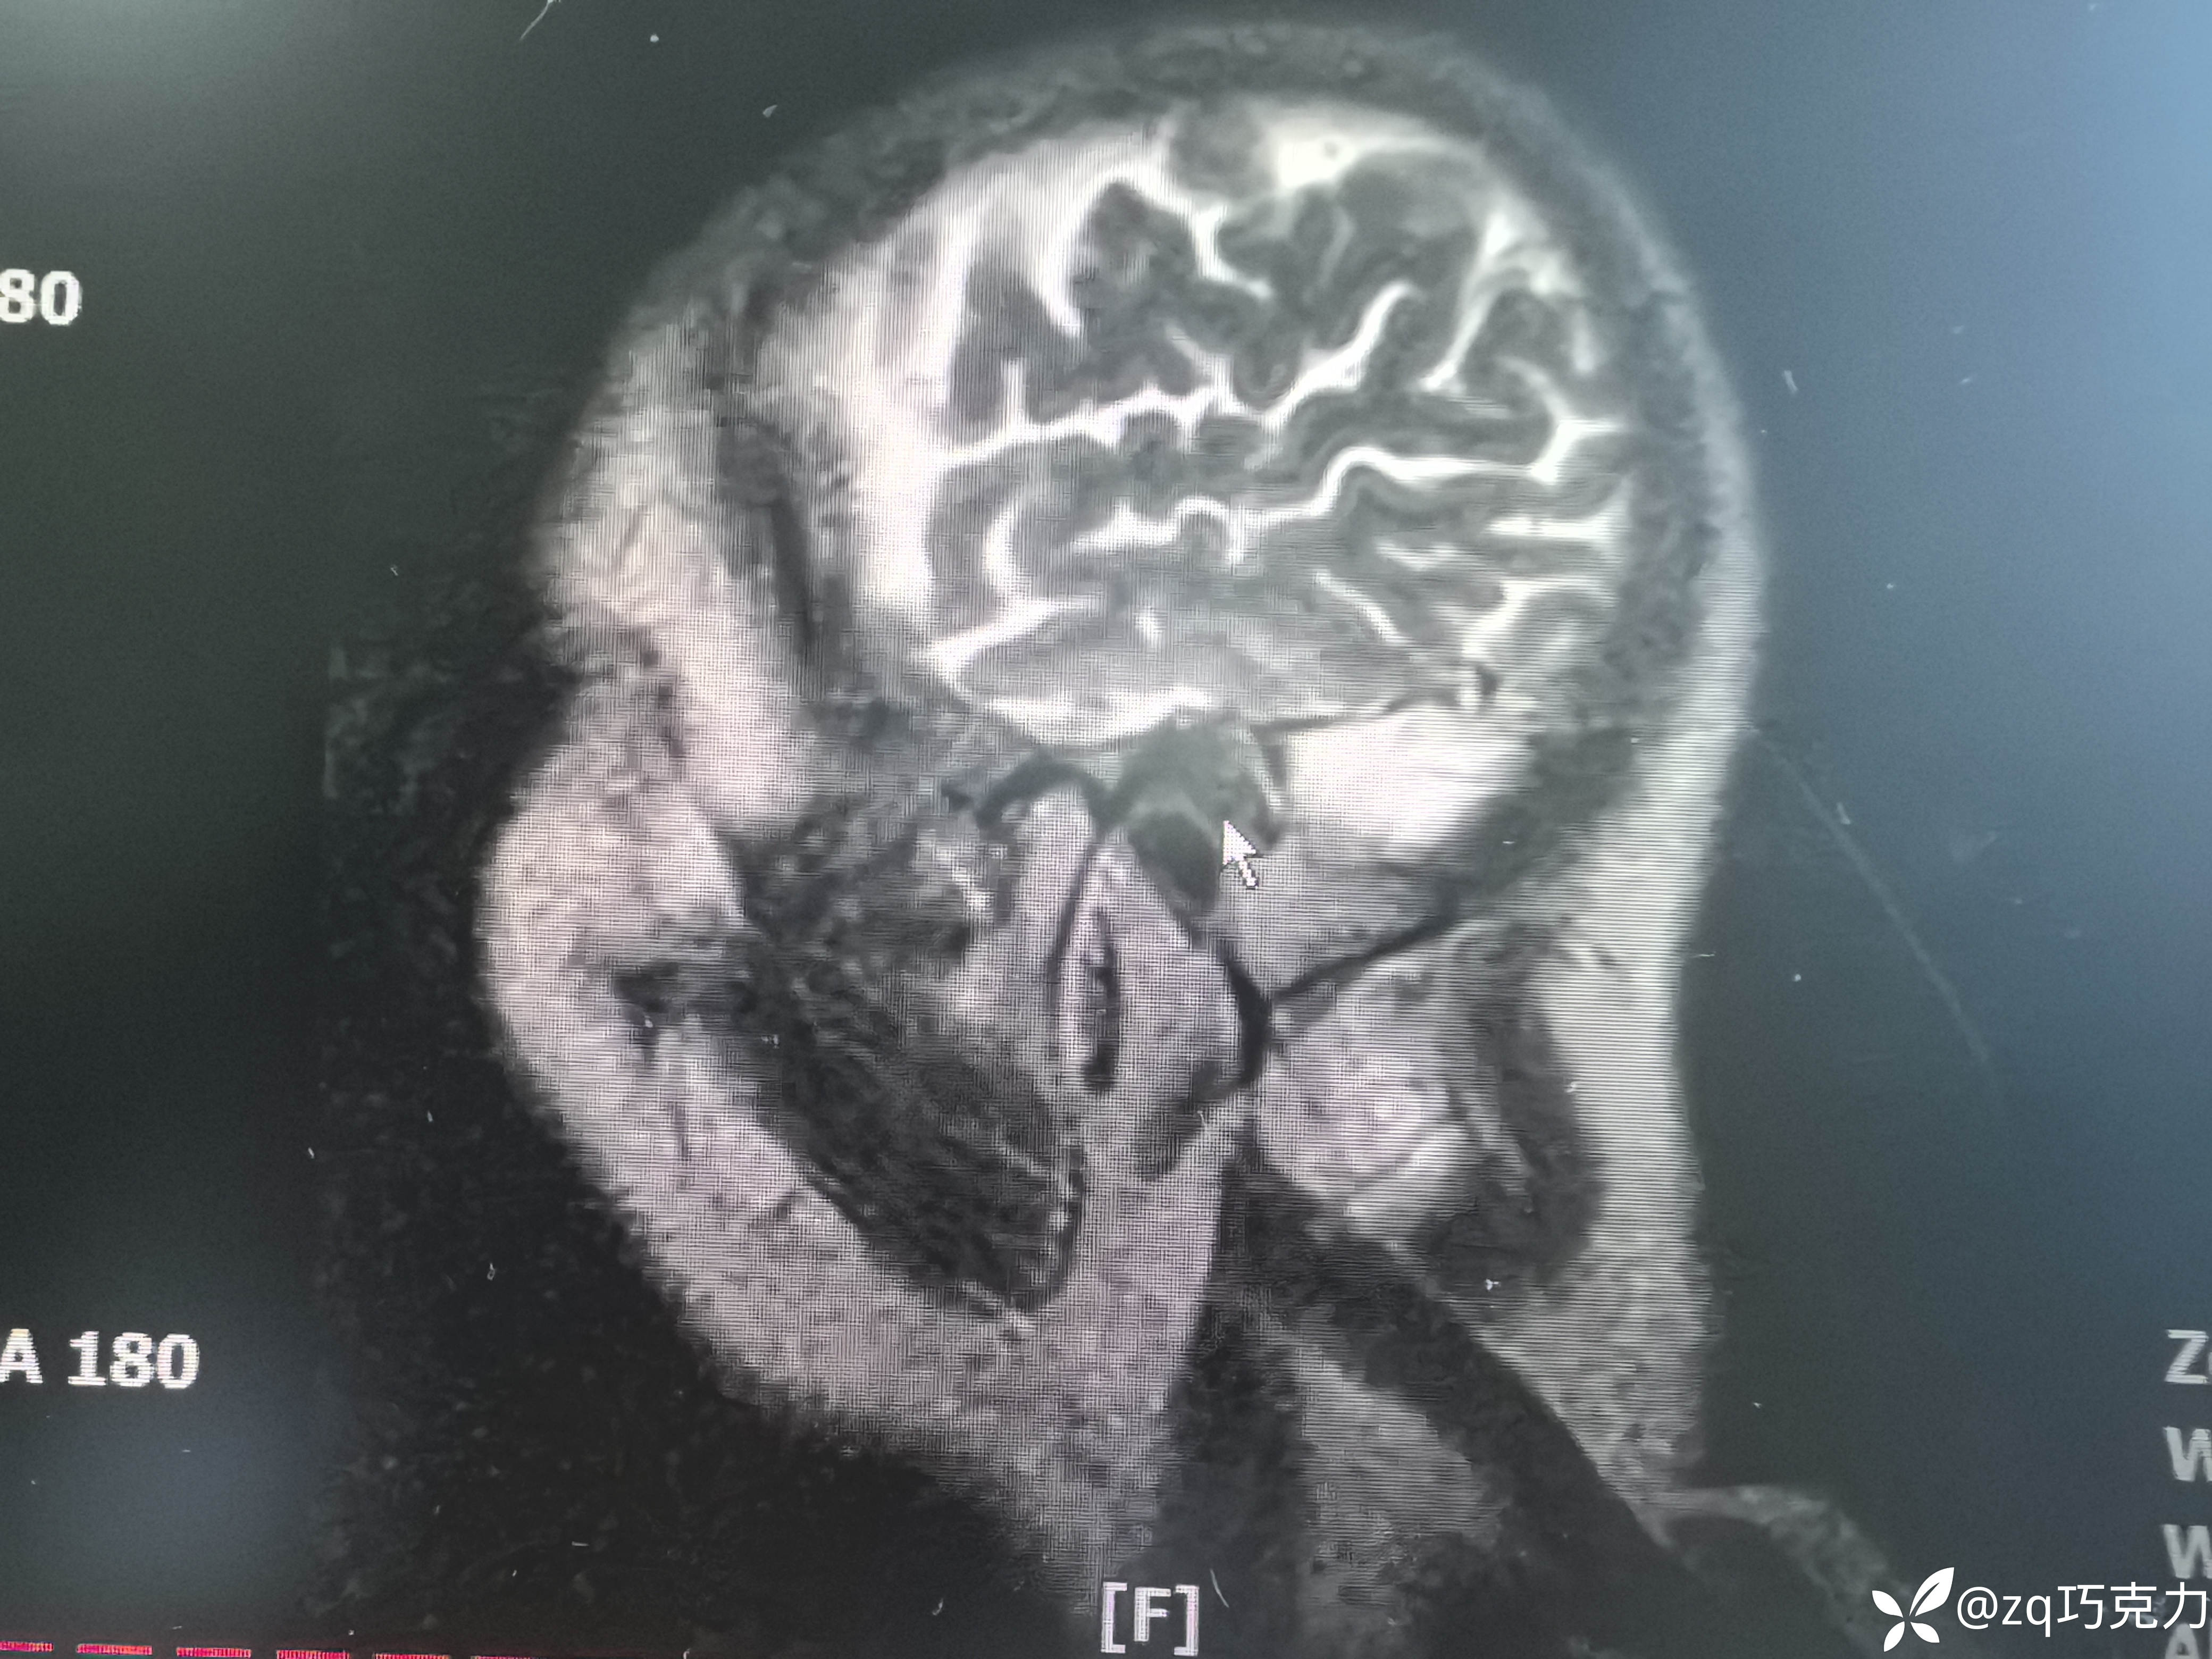

患者老年男性,腰部疼痛伴左上肢左下肢麻木疼痛1年

诊断什么?